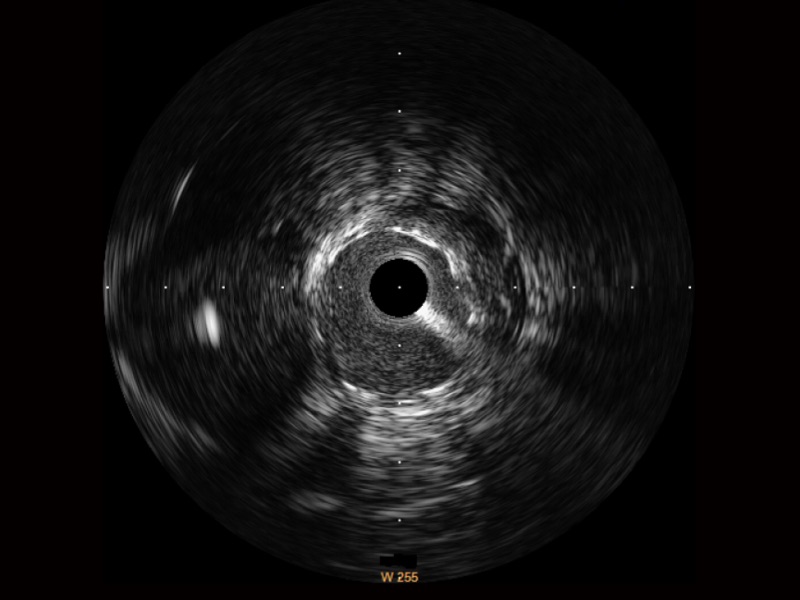

狗万官方网站宽频IVUS图像

传统IVUS图像

对比传统IVUS导管成像,狗万官方网站宽频IVUS图像的近场支架梁显影更细腻,远场中膜外血管仍清晰可辨,兼顾远中近,兼顾分辨力与穿透深度